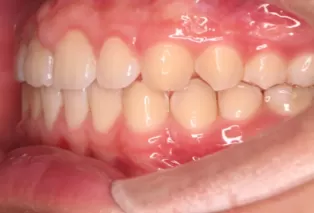

Intraoral photos after treatment